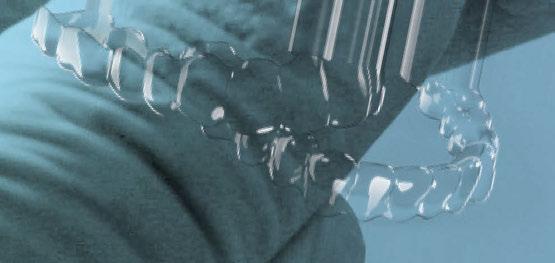

Hoy en día, debido a las altas demandas estéticas de muchos pacientes, la Implantología ha ido evolucionando, sobre todo respecto a protocolos de tratamiento, para poder realizar tratamientos predecibles y exitosos a nivel estético, biológico y funcional. Actualmente disponemos de herramientas digitales (escáneres, CBCT, software de planificación, impresoras 3D, etc.), que nos permiten optimizar tanto la fase previa de estudio y planificación como la fase quirúrgica y protésica posterior. Estas herramientas toman un papel importante en los casos de Implantología inmediata y provisionalización inmediata, pudiendo preparar previamente a la cirugía, guías quirúrgicas y provisionales de carga inmediata (1).

Cuando debemos de afrontar un caso de Implantología múltiple y provisionalización inmediata, todos estos factores cobran aún más importancia (7-9). Como explicaremos a continuación en el caso clínico, para lograr un resultado óptimo, deberemos iniciar nuestro tratamiento a partir de encerados digitales, que nos permitan simular la rehabilitación definitiva (10). A partir de aquí podremos planificar la posición tridimensional correcta de nuestros implantes protéticamente guiados, ayudándonos de guías quirúrgicas, tanto en las regeneraciones óseas previas como en la cirugía implantológica.

A continuación, para la planificación de los implantes dentales y el diseño de la férula de cirugía guiada se usó la plataforma digital RealGUIDE®. Para ello se realizó el matching, por un lado, del archivo STL del encerado digital; y, por otro, del archivo 3D. De esta manera, se pudo analizar el tejido óseo residual apical a cada diente y la posición de la raíz respecto a las corticales vestibular y palatina. También se estudió la relación de los contornos óseos con los tejidos blandos y con la posición final de los márgenes cervicales de la restauración protésica, pudiendo así planificar la posición 3D correcta de los implantes. En esta primera fase se diseñó una férula quirúrgica para la elevación de seno bilateral a partir del software RealGUIDE™, que nos sirvió de guía para el diseño de las ventanas de acceso. Esta férula se imprimió con la impresora 3D Formlabs® (Figura 7)